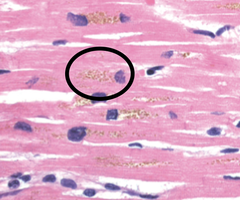

What is lipofuscin?

Front

Wear and tear pigment that accumulates in the liver due to peroxidized lipids; it is commonly present in hepatocytes and cardiac myocytes

Back